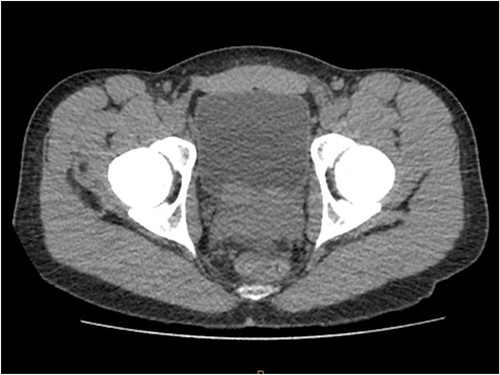

Laboratory tests of full blood count and liver function test were unremarkable with prostate specific antigen of 0.53. Mid-stream urine MCS did not show any infection and urine cytology was negative. Renal function test revealed progressive worsening of previously normal eGFR down to 27 ml/min. Initial renal tract ultrasound (Fig. 1) showed enlarged prostate indenting into the bladder base with high post micturition urine residual volume of 185 ml but no hydronephrosis. CT KUB (Fig. 2) showed irregularly enlarged prostate with bilateral hydroureteronephrosis. MRI prostate showed enlarged prostate with PIRADS 5 amorphous mass suspicious for carcinoma involving bilateral seminal vesicles and right vesicouretric bladder. FDG PET (Fig. 3) showed unusual distribution pattern of lymphoma involving the prostate with bilateral symmetrical renal, early pulmonary, and possibly right thyroid lobe involvement.

PET FDG scan pre-R-CHOP chemotherapy showing disease activity in the prostate.